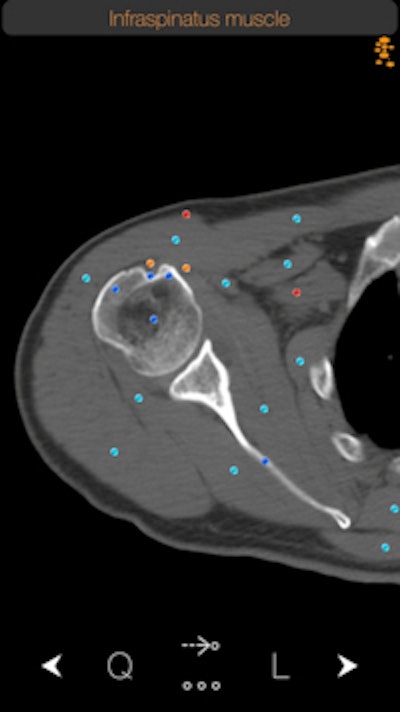

AuntMinnie.com presents the next article in an ongoing series highlighting notable mobile apps in radiology. In this installment, we take a look at CT Anatomy, an iOS app that offers a cross-sectional guide of normal anatomy as seen on CT. It includes more than 350 axial CT views with anatomy, as well as more than 700 anatomical structures along with descriptions, according to developer iCat Medical Software, a U.K.-based mobile app firm.

CT Anatomy helps educate the user on normal human anatomy as seen on the CT. By learning normal CT anatomy, you are taking the first step toward correct diagnosis.

A CT Anatomy app can't deviate much from its intended purpose, which is to demonstrate the anatomy of the human body. It has to be complete and comprehensive. However, sometimes a single anatomical name does not give you the whole picture of that structure. So we have taken this one step further by including information in a very easy and nonobstructive way about the anatomical structure you are searching for.

Another feature that I personally like a lot is what we call FollowMe mode. Looking at a 2D image and trying to figure out where an anatomical structure comes from or goes to is sometimes difficult. With CT Anatomy, the user can follow an anatomical structure through its course and understand better its relationship with other adjacent structures.